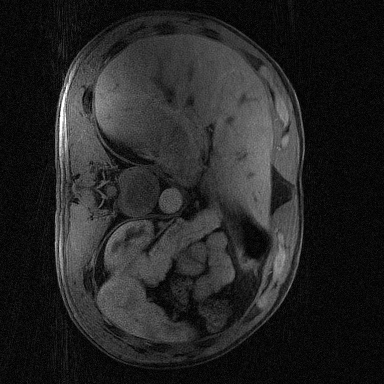

Supervised Deep-Learning (DL)-based reconstruction algorithms have shown state-of-the-art results for highly-undersampled dynamic Magnetic Resonance Imaging (MRI) reconstruction. However, the requirement of excessive high-quality ground-truth data hinders their applications due to the generalization problem. Recently, Implicit Neural Representation (INR) has appeared as a powerful DL-based tool for solving the inverse problem by characterizing the attributes of a signal as a continuous function of corresponding coordinates in an unsupervised manner. In this work, we proposed an INR-based method to improve dynamic MRI reconstruction from highly undersampled k-space data, which only takes spatiotemporal coordinates as inputs. Specifically, the proposed INR represents the dynamic MRI images as an implicit function and encodes them into neural networks. The weights of the network are learned from sparsely-acquired (k, t)-space data itself only, without external training datasets or prior images. Benefiting from the strong implicit continuity regularization of INR together with explicit regularization for low-rankness and sparsity, our proposed method outperforms the compared scan-specific methods at various acceleration factors. E.g., experiments on retrospective cardiac cine datasets show an improvement of 5.5 ~ 7.1 dB in PSNR for extremely high accelerations (up to 41.6-fold). The high-quality and inner continuity of the images provided by INR has great potential to further improve the spatiotemporal resolution of dynamic MRI, without the need of any training data.

翻译:在这项工作中,我们建议了一种基于IRI的方法,用这种方法来改进动态磁共振感应成像(MRI)重建,而该方法只是以高度低劣的 k-空间数据为基础,而该数据仅以磁共振坐标作为投入。具体地说,拟议的IRI将动态MRI图像作为一种隐含功能来表示,并将其编码到神经网络中。网络的权重仅从稀有的(k, t)空间数据本身中学习,而没有外部培训数据集或先前的图像。 利用基于IRI的强有力隐含性稳定化,同时不以清晰的动态和时空坐标坐标坐标坐标坐标作为投入。 拟议的IRIR将动态MRI图像作为一种隐含功能,将其编码到神经网络中。网络的权重仅从淡化的(k, t)空间数据本身学习,而没有外部培训数据集或先前的图像。